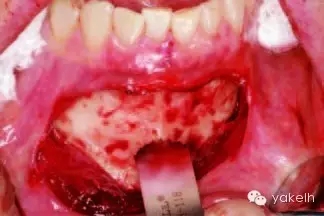

¤¤暴露頦部后,設(shè)計(jì)取骨的切口。取骨塊的大小由受區(qū)所需的骨量決定。骨切開處距離根尖以及頦孔最少應(yīng)有5mm。多數(shù)情況下,要保留下頜骨下緣以及舌側(cè)皮質(zhì)骨的完整性。唇側(cè)皮質(zhì)較厚,其內(nèi)側(cè)的松質(zhì)骨通常較致密。可以使用渦輪手機(jī)碳合金裂鉆(557號(hào)或701號(hào))或者來復(fù)鋸將骨切開(圖13.19)。切透皮質(zhì)骨達(dá)松質(zhì)骨后,用骨鑿將骨塊移除(圖13.20)。用單面鑿沿著骨切開線輕輕敲擊,除了下頜骨下緣,將骨塊從基底部折斷。在中線處時(shí),也可將塊狀骨分割成矩形骨塊,分段獲取。分成兩個(gè)骨塊后更容易獲取,因?yàn)榭梢杂霉氰弻⒌诙K骨塊從舌側(cè)撬起。另外,移除塊狀骨后,還可使用骨刮匙、鑿子、咬骨鉗、環(huán)形鉆獲取

一些松質(zhì)骨,但是松質(zhì)骨的量十分有限。在移除塊狀骨后,可以將止血材料如膠原或明膠海綿置于松質(zhì)骨表面。當(dāng)獲取較大的骨塊時(shí),供區(qū)應(yīng)使用骨替代材料如羥基磷灰石,來維持唇側(cè)的外形(圖13.21)。較少或者顆粒狀的骨移植時(shí),可使用環(huán)形鉆、骨收集器、骨挖器來獲取。把骨塊植入受區(qū)后,再將供區(qū)的傷口縫合,這可以縮短取骨與植骨之間的時(shí)間。分離前庭溝切口上方的黏膜,以減少水腫和下唇運(yùn)動(dòng)所產(chǎn)生的張力。用可吸收縫線分層縫合前庭溝切口(圖13.22)。深層組織使用4-0可吸收線縫合,表層黏膜使用4-0鈷腸線縫合。術(shù)后使用壓力繃帶包扎頦部,以減少水腫、血腫形成及切口裂開(圖13.23)。